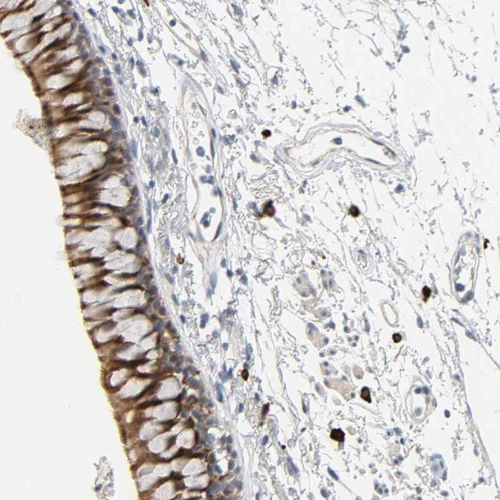

Immunohistochemical staining of human bronchus shows strong cytoplasmic positivity in respiratory epithelial cells.